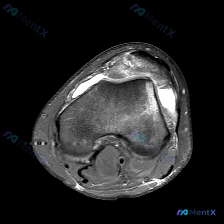

今天看到一份很有警示意义的膝关节MRI读片病例,整理出来和大家分享一下。这是一份经过髌股关节区域的膝关节轴位T2加权MRI,原始问题提示观察「软骨异常」,我们先把影像所见整理清楚: 一、病例基本影像信息 1. 髌股关节区域:髌骨前方及关节周围软组织可见弥漫性高信号,符合水肿/炎性渗出表现;髌股关节外...